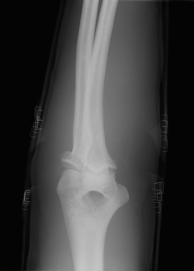

橈骨頭骨折

第1回目、整復後のX-Pです。(左側の写真)

橈骨頭の転位25°の傾斜残存しているので、もう少し戻していく。

第2回目の整復で橈骨頭傾斜18°まで戻りました。(右側の写真)

保存療法の限界25°はクリアしていますので、このまま保存いきます。

ラグビー選手の強靭な体格の患者さんです。

回復力旺盛と思います。